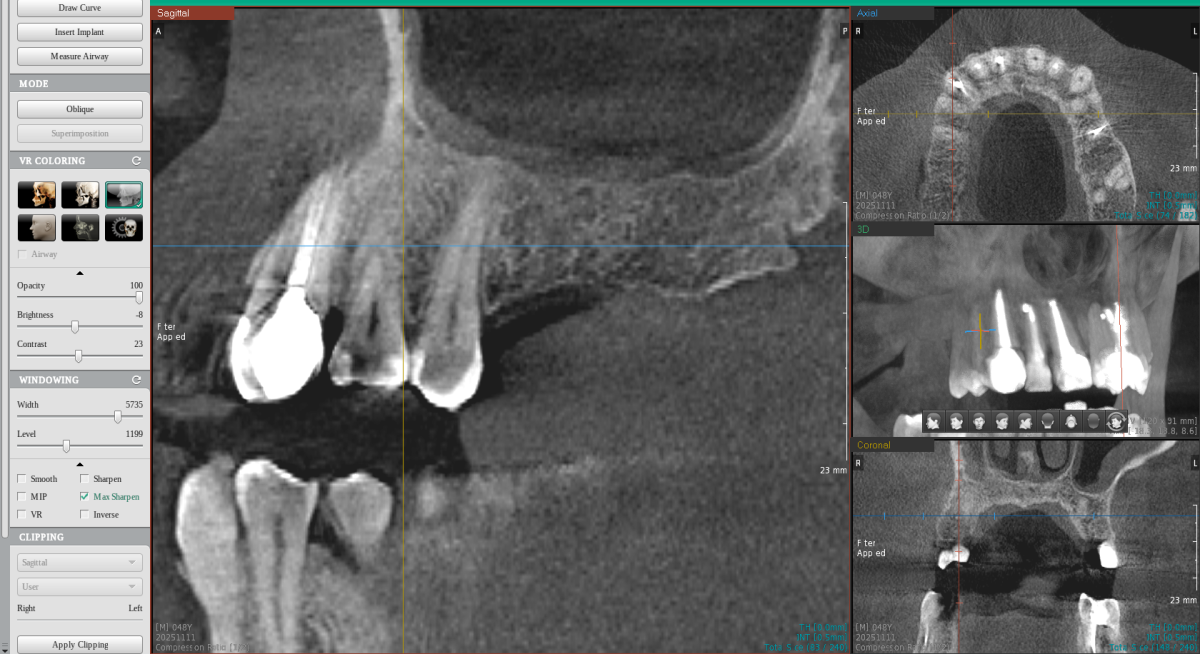

Делали 13 зуб, хронический периодонтит. Дистальная стенка ушла под десну. Делали эндо, врач почему-то решила сразу пломбировать каналы и сделать реставрацию композитом. Ничего не сказала, но на ОПТГ и КТ вот такая картина. Как будто трещина, да? Включая и материал в канале тоже - фрагментация какая-то...

Перелом?